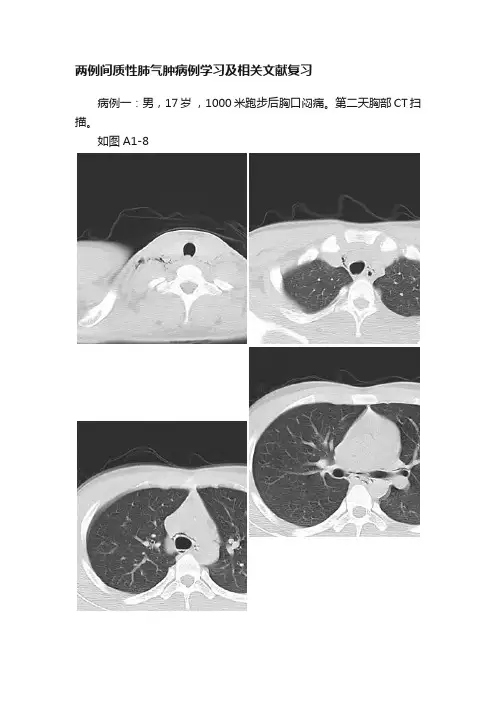

两例间质性肺气肿病例学习及相关文献复习病例一:男,17岁,1000米跑步后胸口闷痛。

第二天胸部CT扫描。

如图A1-8图A1-8:双侧颈部、纵隔区及沿双侧支气管血管束周围见多发条形气体密度影包绕。

病例二:男,17岁,打篮球中突发胸痛,胸部CT扫描。

如图B1-8图B1-8:右肺尖、双侧肺门支气管血管周围、纵隔、右侧胸壁、双侧颈部均可见气体密度包绕,右肺尖局部见肺组织压缩带。

一.病例分析:1.两例都为年轻患者,都有典型的运动受伤及胸痛病史。

没有基础疾病的记载,影像上也没有其他基础疾病的发现,如肺大泡、肺气囊及其他间质改变。

2.双肺沿血管支气管束走行气体密度影,经肺门、纵隔、胸廓入口,扩散至颈部、上胸部等皮下软组织内……此为经典的肺间质气肿影像学表现及扩散途径!二.关于肺间质气肿1.基础病理为肺泡破裂,气体逸出途径有二:经肺表面进入胸腔——气胸或血气胸进入肺间质——肺间质气肿2.病因多方面:外因,包括剧烈运动、冲击、咳嗽、正压通气、气浪、有害气体、溺水等等。

内因,发育缺陷、Birt-Hogg-Dube综合征、肺大泡、肺气囊、间质性肺炎或其他众多累及肺间质的病损,尤为值得一提的是“抗MDA5抗体阳性皮肌炎-肺间质改变”,往往进展迅速,预后不良!3.临床与影像:患者常有突发的胸痛、胸闷、咳嗽症状,部分患者可提供外伤史。

颈胸部皮下气肿很容易被临床查体发现—典型的皮下捻发音!影像的任务是确定气体来源和查找可能存在的原发病变。

文献学习:概念:间质性气肿多为肺泡破裂,空气进入支气管和血管周围间质,再肺门进入纵隔,产生纵隔气肿。

溢入肺间质内的气体沿间质间隙进入纵隔,形成纵隔内积气,气体又沿纵隔内结缔组织间隙上行至颈、肩、腋等部位的结缔组织间隙后产生皮下气肿。

间质性肺气肿临床上并非多见,在日常影像诊断工作中若对此病的表现特点认识不足,极易造成误诊或漏诊。